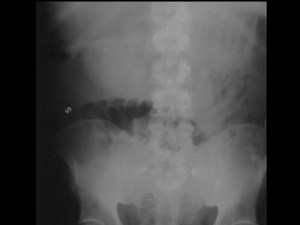

Bowel obstruction is considered to be present at CT when distended bowel loops are seen proximal to collapsed loops. When a point of transition from dilated

X-Ray Sunday Small Bowel Obstruction | CTisus: Cutting edge information on body CT (Computed tomography). | Facebook